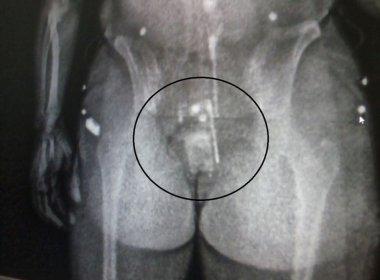

Nervosa ao passar pela revista

íntima antes de entrar no Conjunto Penal de Teixeira de Freitas (CPTF), uma

mulher foi flagrada por agentes com um celular na vagina. De acordo com o site

Rastro101, o flagrante aconteceu nesta quinta-feira (4). A acusada é moradora

do bairro de Colina Verde, e, após o fato, foi encaminhada para a Sede da 8ª

Coordenadoria Regional de Polícia do Interior (COORPIN), onde prestou

depoimento. De acordo com informações, essa não seria a primeira vez que

Larissa tentar entrar na unidade prisional com aparelho celular nas partes

íntimas.